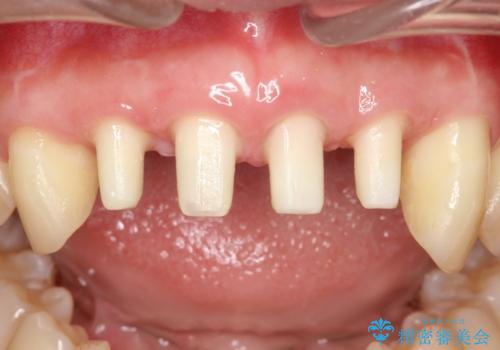

侵襲性歯周炎。前歯の歯周補綴

- 前歯がグラグラすることを主訴に来院されました。

再生治療後、歯周補綴を行っております。

(根管治療はDr河野にて施術)

歯周病が進行してしまった歯に対し、再生治療および歯周補綴を行うことで歯周組織の安定を得ることができました。